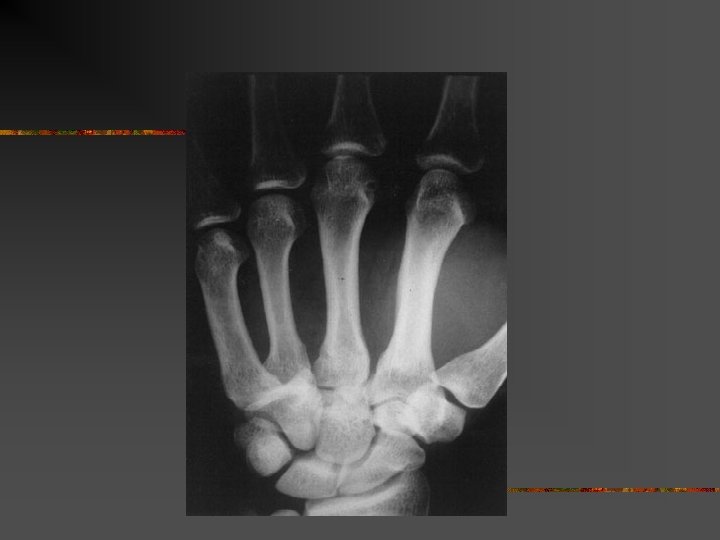

Luxation M 4 M 5

Radiographie n Sur la radio de face il faut cher l’interligne carpométacarpien

Radiographie n Sur le profil il faut recher un décalage postérieur

Radiographie n n Face+profil+3/4 Scanner en cas de doute Profil stricte